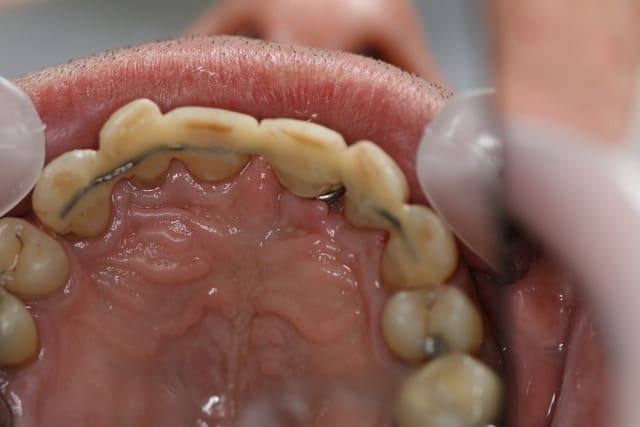

Les attelles d'Abjean j'en pose chaque semaine (ou presque), l'avantage ENOOOOORME par rapport à un "jonc noyé" c'est la rétention 3D que tu n'as pas avec le jonc!

et le délabrement est bcp moindre, en plus quand une attelle lache tu la changes, et pas tout le bastringue!

les miennes tiennent plus de 10 ans...

J'aime beaucoup mon "bridge provisoire" suite à la luxation de la 31 avec fracture de l'apex...^^ elle a tenu 8 ans.

En attendant, ce type de contention transitoire pendant une phase de guérison parodontale après TT ortho (suite aux migrations dentaires) est idéale à mon avis.

Après tu vois ça comme du bricolage: chez casto y a tout c'qui faut ! ^^

Ben si en fait, c'est la seule:

1 a être discontinue (donc refaisable sans tt déposer encore une fois)

2 a avoir une rétention axiale, vestibulo palatine, et disto mésiale (3 axes)

3 assez facile à mettre en oeuvre (par rapport à la manipulation d'un long fil que tu colles d'un bout qu'il faut tenir pour ne pas qu'il bouge :(....

4 délabrement moins important et risque de fracture de la dent bcp moindre (bord incisal par exemple)

5 résultat immédiat esthétique et absence d'interférences occlusales car entièrement incluse dans les puits et sillons réalisés.

Ca dépanne super bien dans le cas de la luxation en urgence en attendant la conjointe.